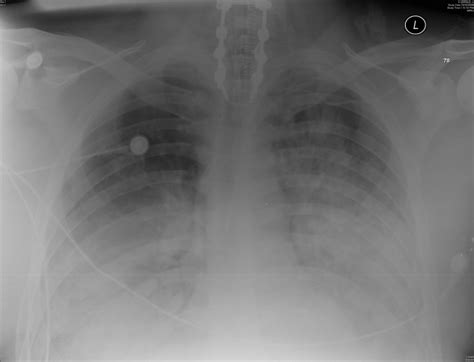

ARDS is a complex syndrome that can be triggered by various factors, including sepsis, pneumonia, trauma, and aspiration. It is marked by the rapid onset of bilateral pulmonary infiltrates, refractory hypoxemia, and decreased lung compliance. The Ards Chest X Ray is instrumental in visualizing these pulmonary infiltrates, which appear as diffuse, bilateral opacities on the radiograph.

The Ards Chest X Ray is often the first imaging modality used to evaluate patients suspected of having ARDS. It provides a quick and relatively inexpensive way to assess the lungs for signs of inflammation and edema. Key findings on an Ards Chest X Ray include:

• Bilateral pulmonary infiltrates

• Diffuse opacities

• Air bronchograms (air-filled bronchi surrounded by consolidated lung tissue)

• Absence of pleural effusions or cardiomegaly

These findings, when combined with clinical criteria such as the PaO2/FiO2 ratio (the ratio of arterial oxygen partial pressure to fractional inspired oxygen), help confirm the diagnosis of ARDS.

• Bilateral Infiltrates: ARDS typically presents with bilateral, diffuse infiltrates that are often more pronounced in the dependent lung zones.

• Air Bronchograms: These are visible air-filled bronchi within consolidated lung tissue and are a hallmark of ARDS.

• Absence of Pleural Effusions: Unlike other causes of pulmonary edema, ARDS is usually not associated with significant pleural effusions.

• Cardiomegaly: The heart size is typically normal in ARDS, helping to differentiate it from cardiogenic pulmonary edema.